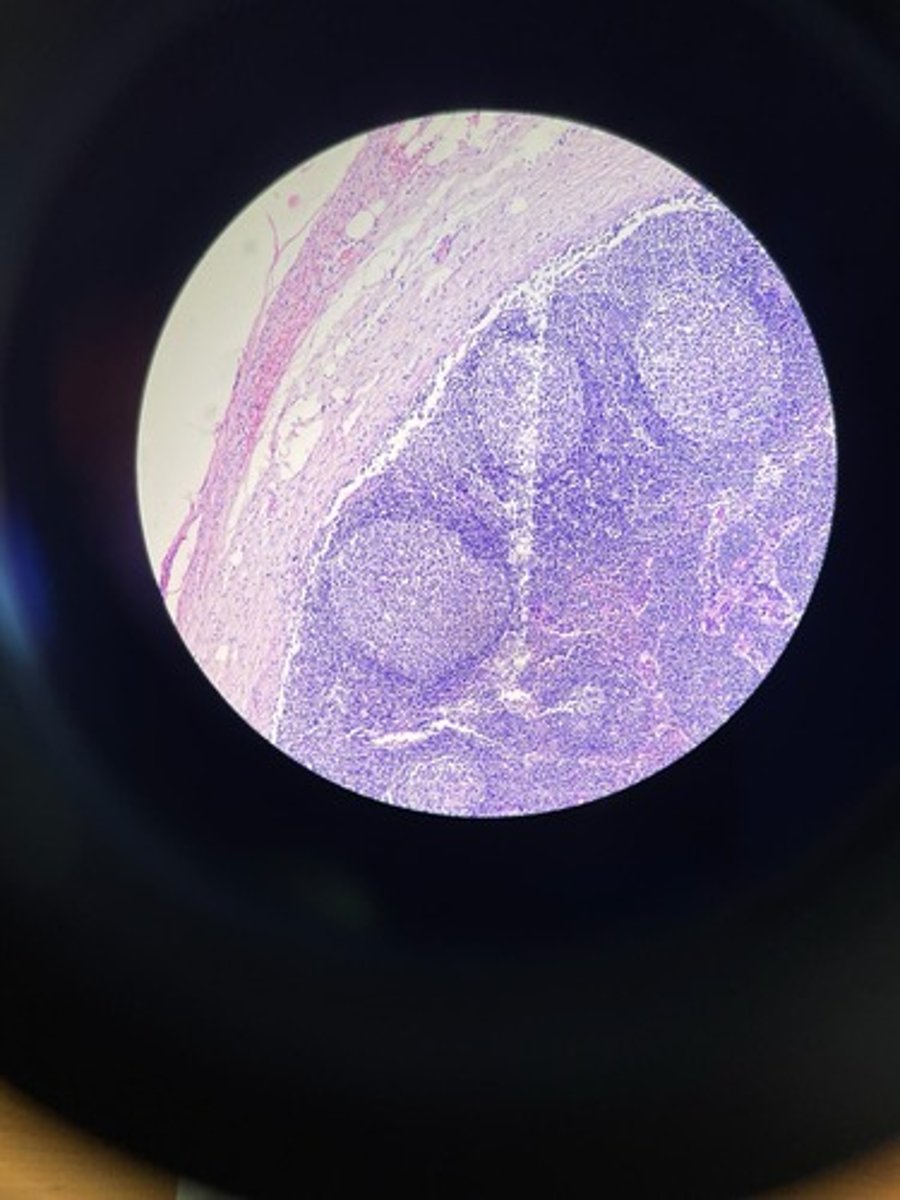

Thymus HE

Thymus HE

Thymus HE

Thymus HE

Thymus HE

Thymus HE

Thymus HE

Thymus HE